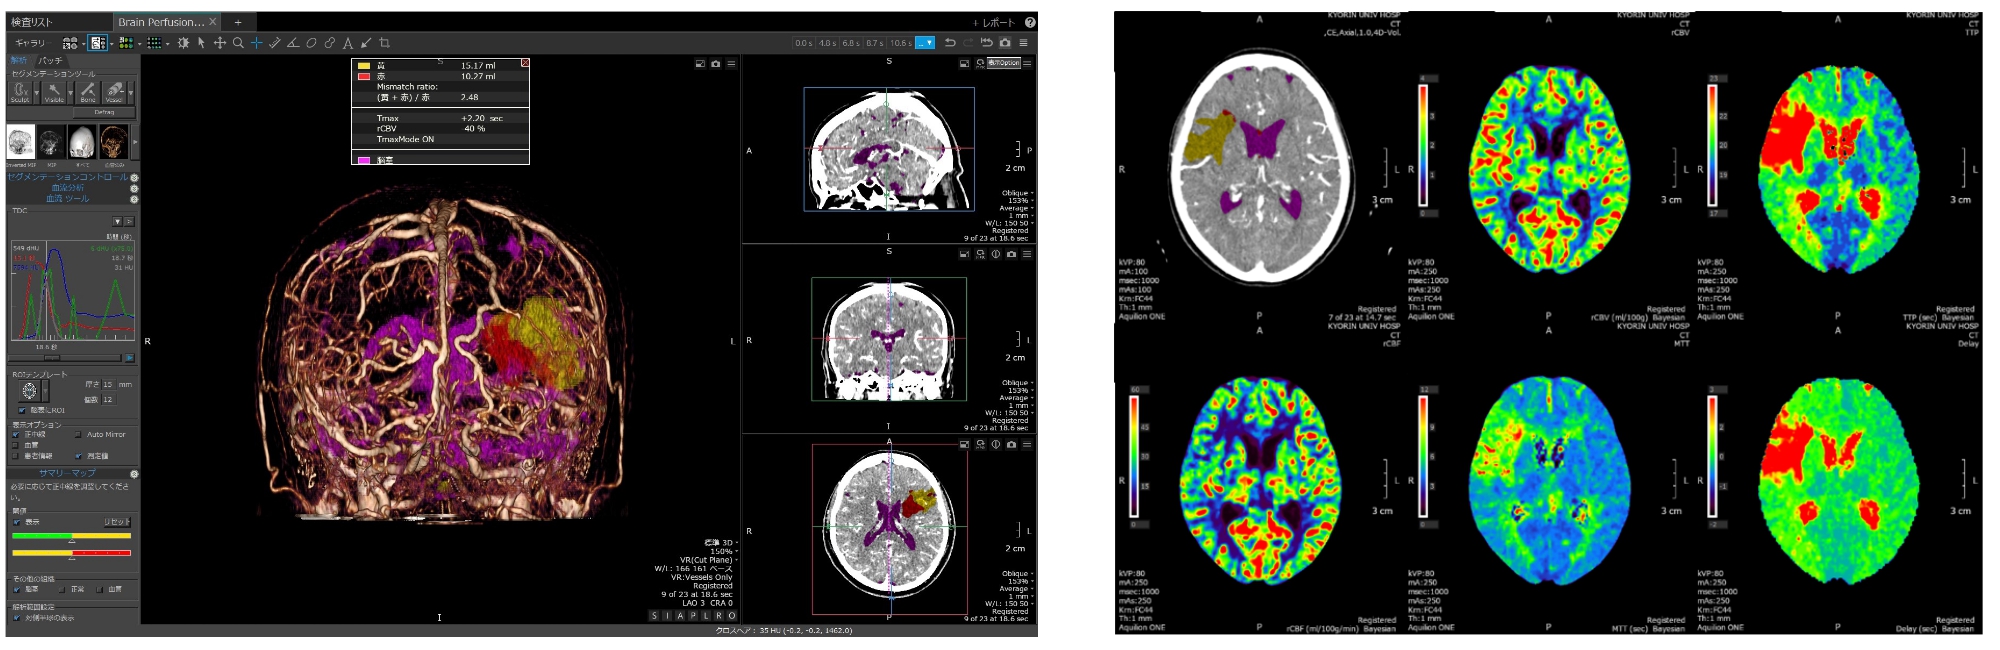

脳卒中患者さんに対する従来の検査方法はCTを撮影してからMRIを撮影し、確定診断をしていましたが、2019年に当院脳卒中センター、放射線部とキヤノンメディカルシステムズ株式会社とが共同で開始した研究により、CTのみで脳血管の梗塞部位を特定することができるようになりました。

脳は血液が途絶えると1分間で190万もの細胞が失われるといわれています。t-PA治療、超急性期血行再建術は24時間365日対応可能です。

MRI/Aを用い、t-PA治療の適切な使用、また、機能予後を考慮した血行再建のタイミングを常に考え、各症例に応じた治療を行っています。